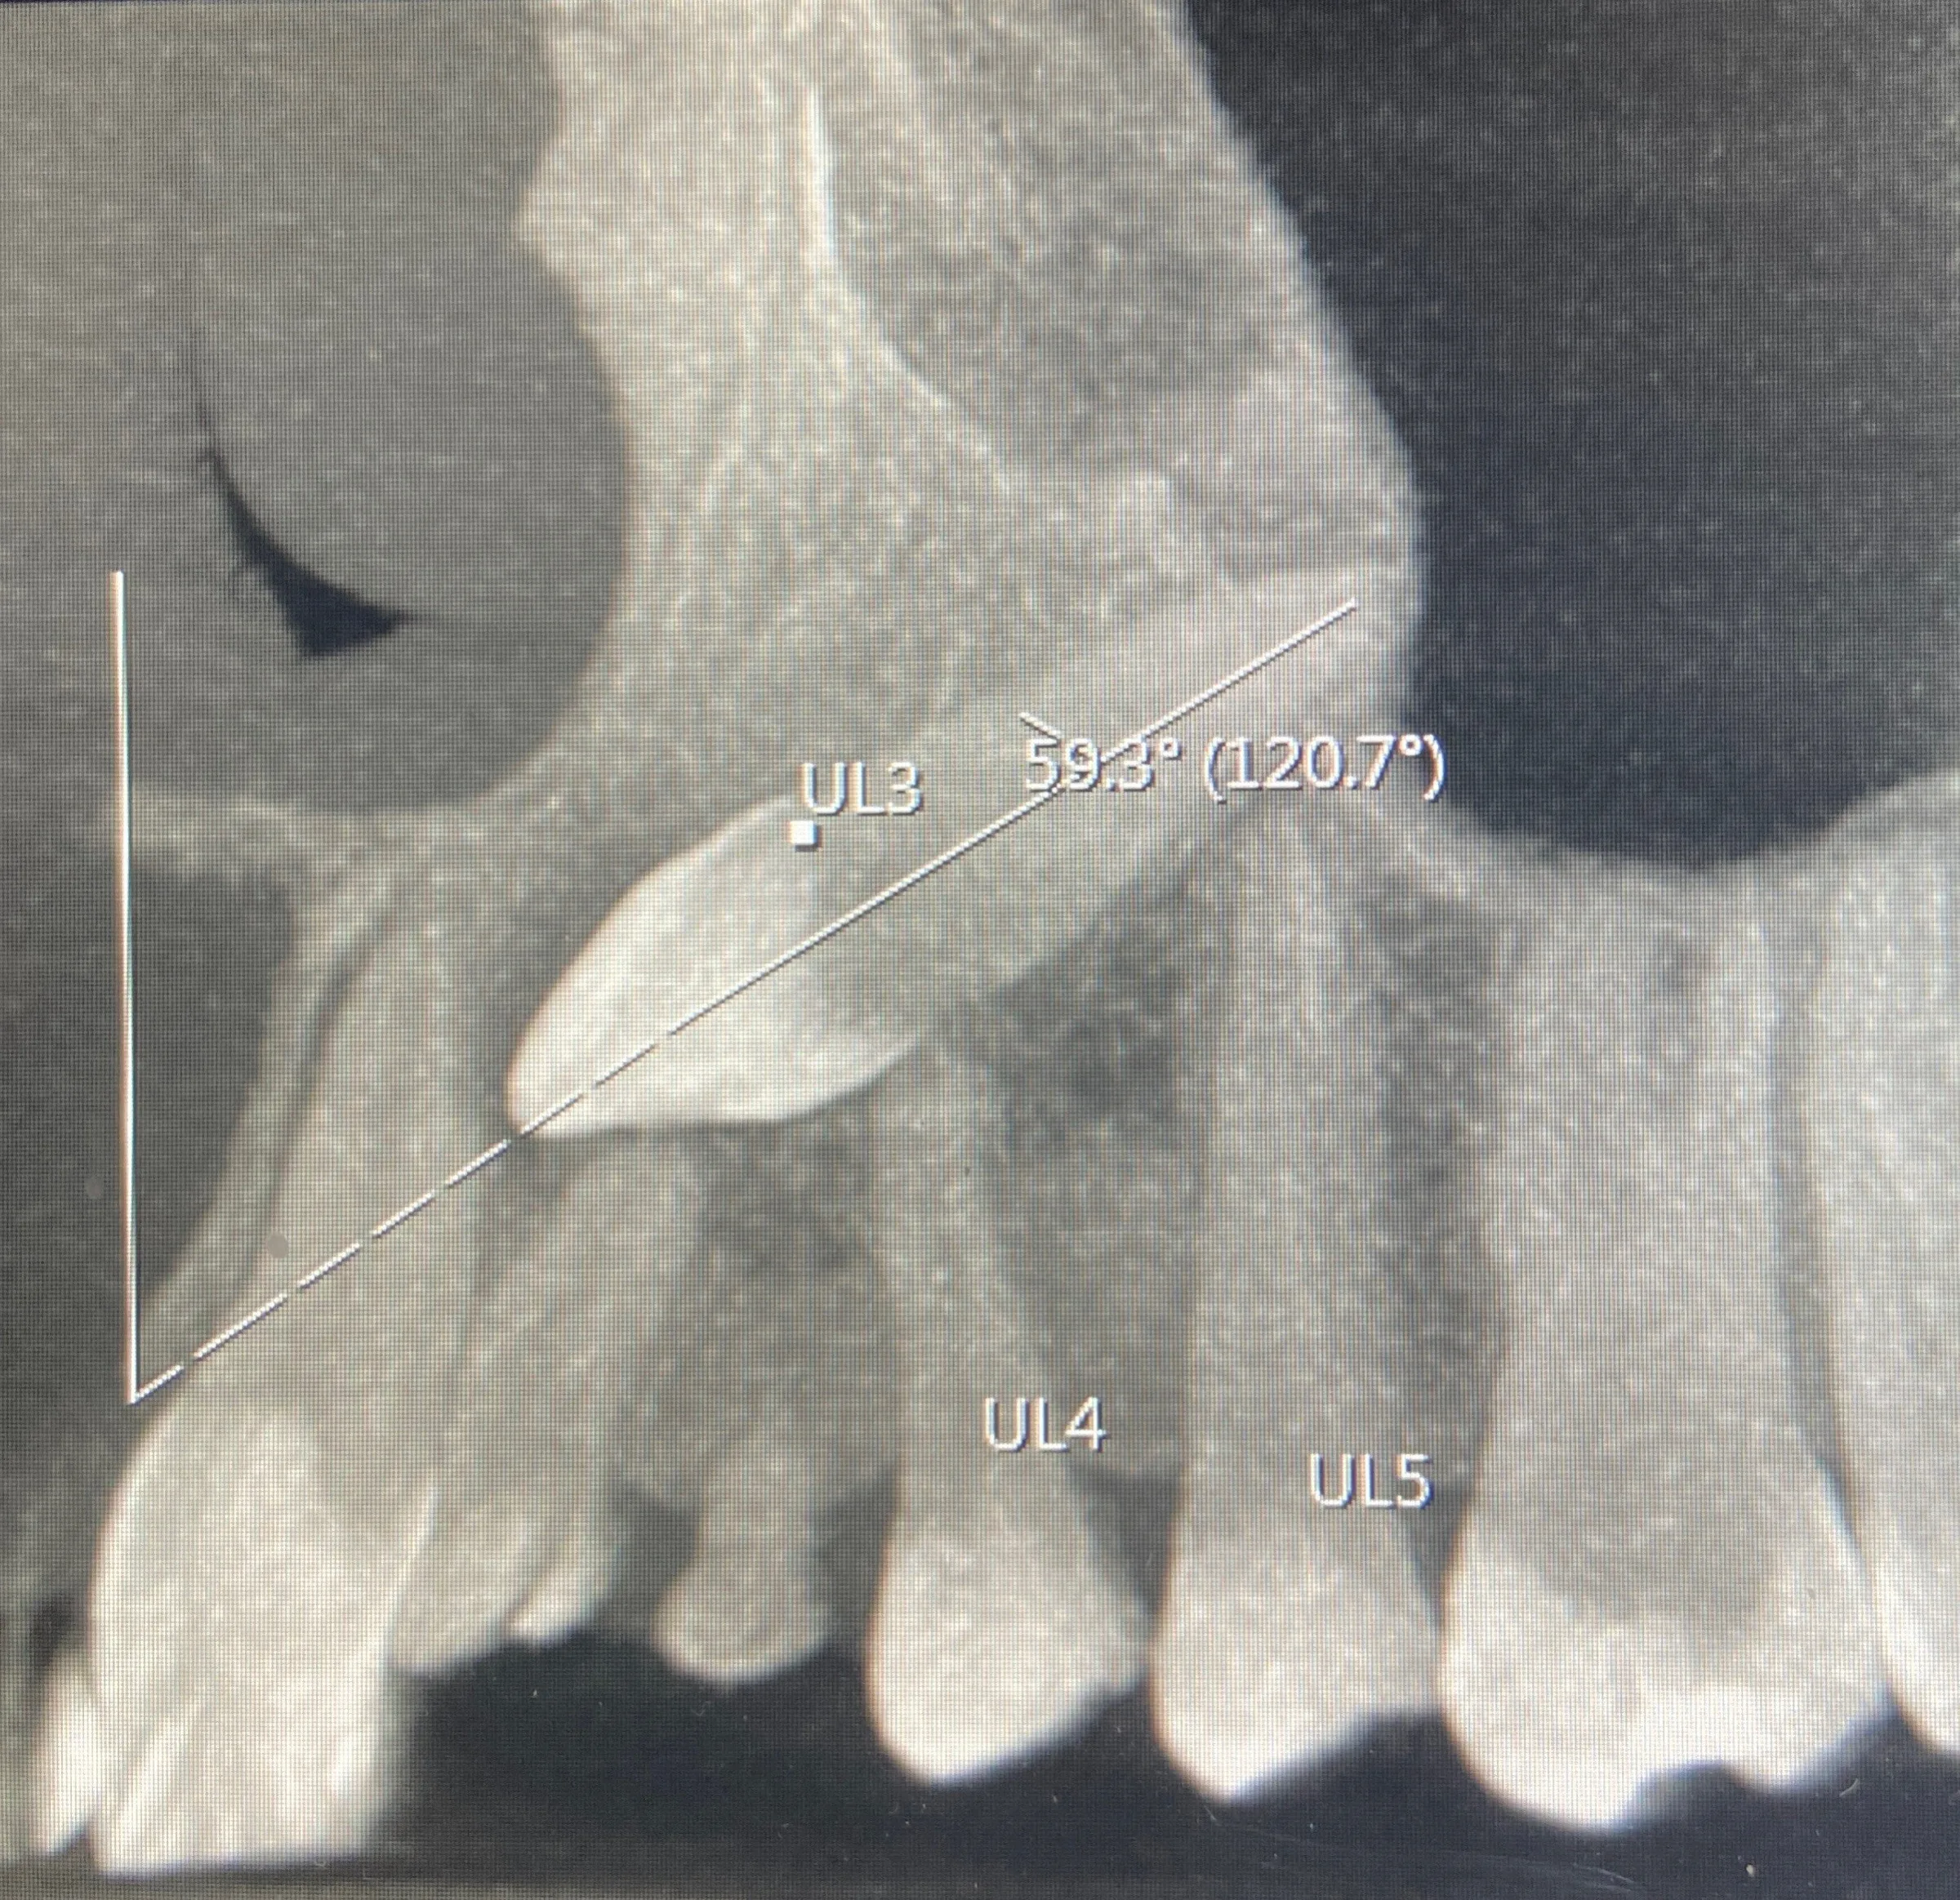

2. Key Image Capture™

• Innovative and proprietary algorithm

• Produces key images from dataset for impacted teeth applications

• Able to be manipulated, annotated and verified by the radiologist

• Report crafted using Report Wizard™

The Report Wizard™ code outputs the key images to further enhance the algorithm accuracy.

60027975173 021 F45 A6 2 D20 4 D53 AF24 FC3956 C4979 F